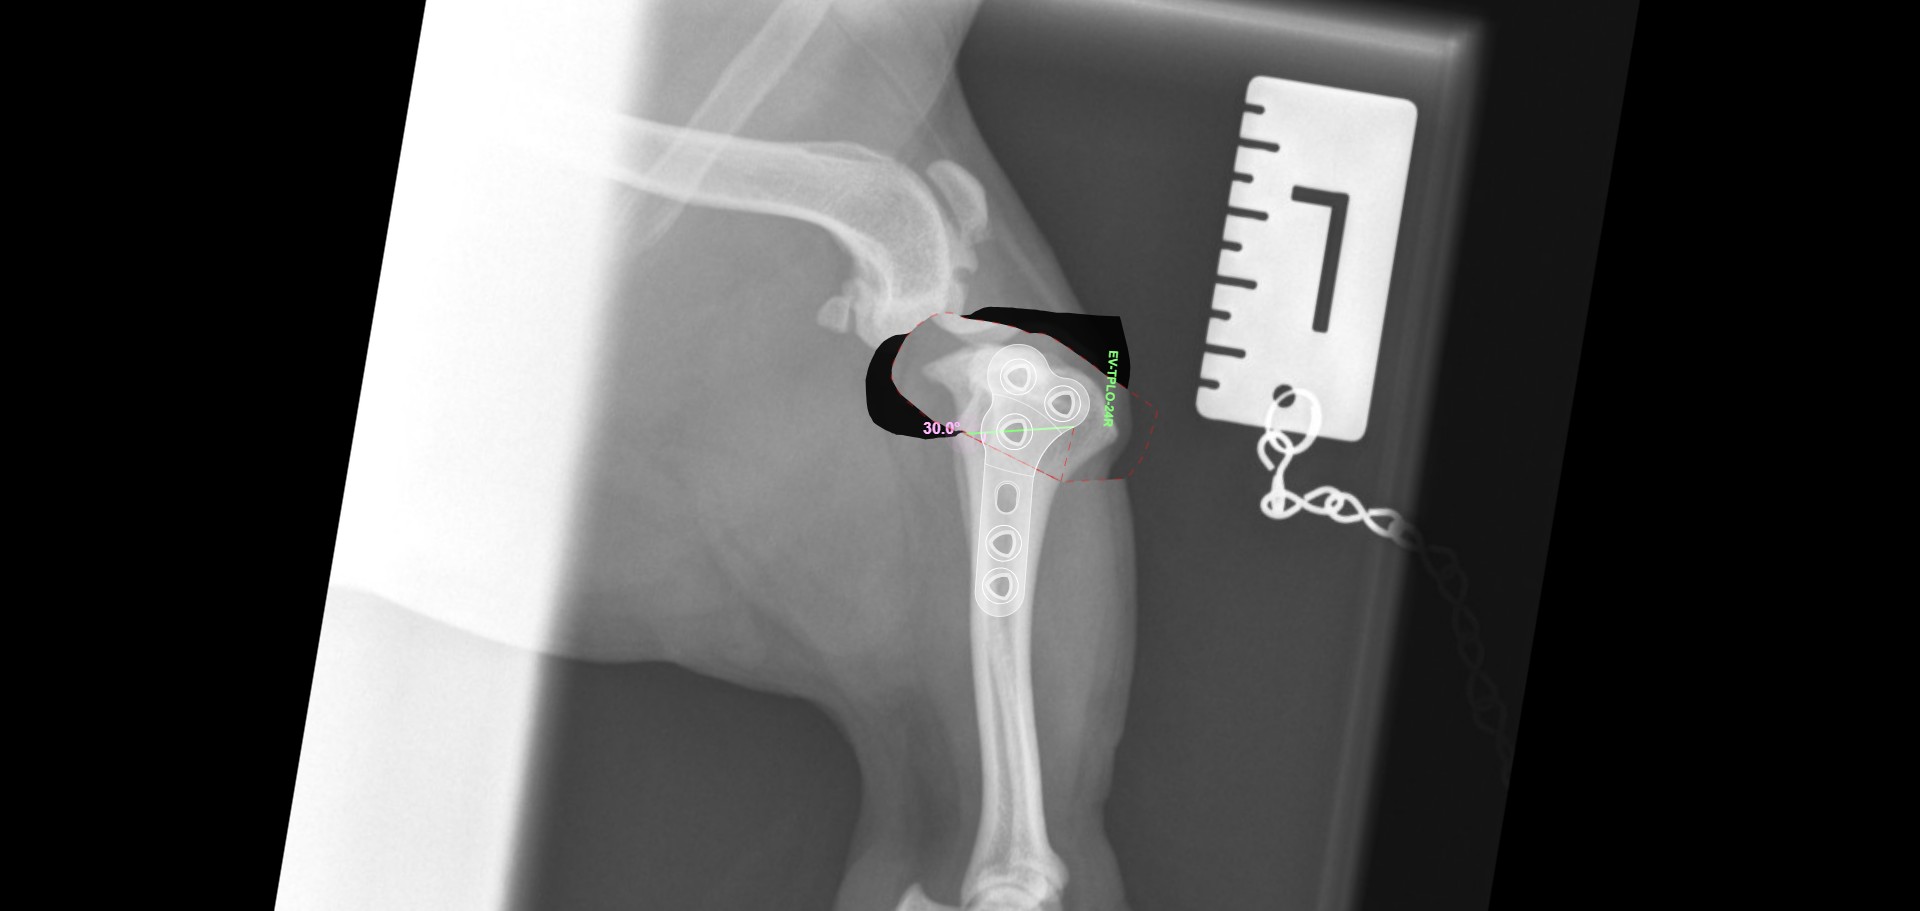

Cranial Closing Wedge

Pre-operative plan

Cruciate ligament surgery - Lateral Suture/TTA/CCWO

Cruciate ligament disease is very common, however, the best management is not certain. Various techniques are employed to best manage the problem in your pet, accounting for their individual anatomy and in discussion with you.